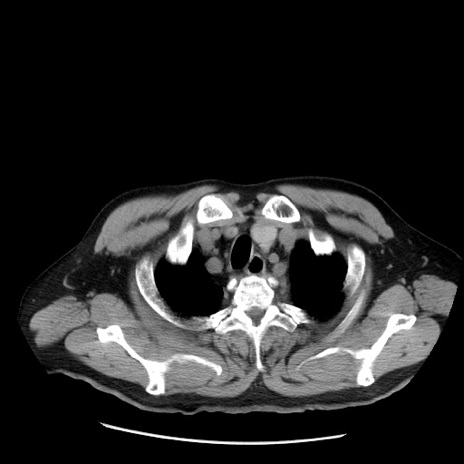

症例20(横断像)

【症例】 60歳代男性

【主訴】 腹部膨満、嘔吐

【現病歴】5日前頃より倦怠感を認め食事量減少し4日前の朝嘔吐、食事摂取困難となった。 3日前近医受診し点滴施行され整腸剤などを処方された。 当日他院を受診し、腹部膨満著明、炎症反応の上昇(CRP10.8、WBC11200)あり、紹介受診となる。

【身体所見】 意識JCS1 受け答えがはっきりしないBP 111/57mHg、 P 67bpm、、BT35.2°C、SpO2 97%(RA)、 腹部:膨隆、打診で鼓音あり、全体的に圧痛有り、腸蠕動音(-)、反跳痛ははっきりせず。

【データ】WBC 11400、CRP 14.20